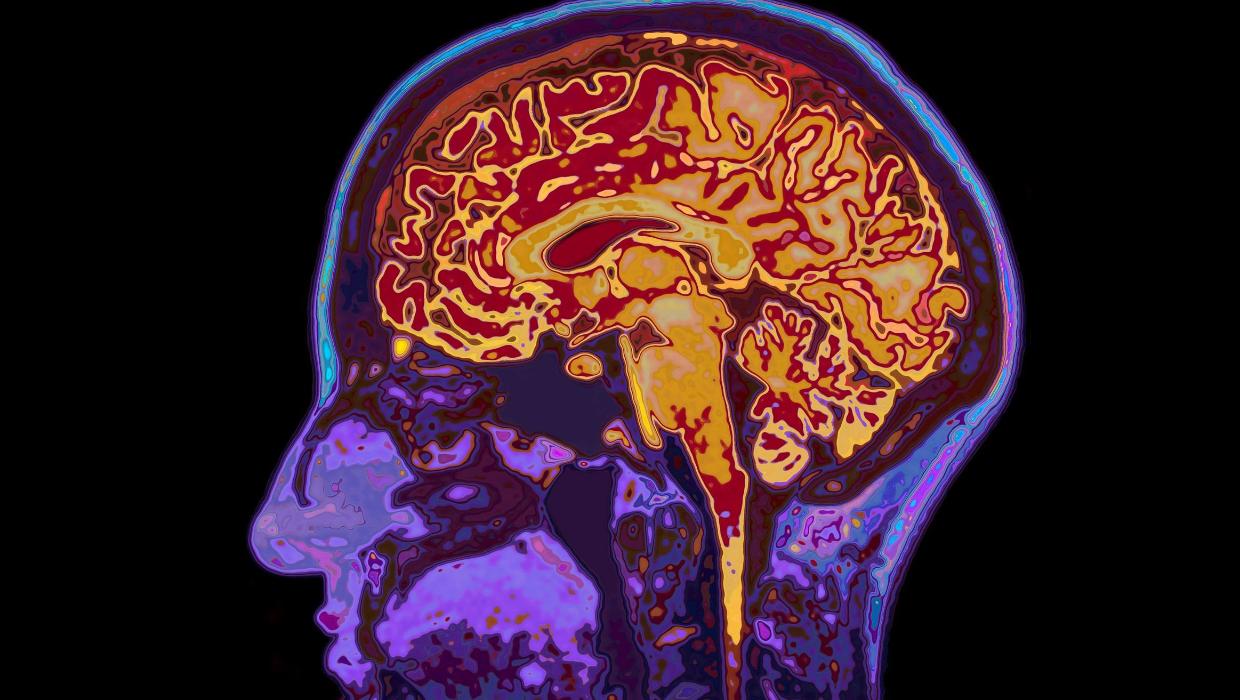

Study Reveals Brain Maturity Extends to Age 32, Aging Begins at 66

Recent research from the University of Cambridge provides new insights into brain development, revealing that human brains remain in a state of adolescence until the age of 32. The study identifies five significant epochs of brain maturation, with four key turning points marking critical stages in a person’s life.

The research highlights that our brains undergo transformative changes throughout various life phases, affecting not only cognitive abilities but also emotional development. According to the study, these epochs include early childhood, adolescence, early adulthood, midlife, and later adulthood, with distinct characteristics defining each period.

In early childhood, the brain is highly adaptable, forming connections rapidly as children learn and explore their environment. Entering adolescence, the brain continues to evolve, with important developments in areas related to decision-making, impulse control, and social interactions. The research emphasizes that this period is crucial for identity formation and emotional regulation.

As individuals transition into early adulthood, significant neural changes occur that enhance cognitive functions such as planning and reasoning. The findings indicate that even into the thirties, the brain retains a level of plasticity, allowing for continued learning and adaptation. This challenges previous assumptions about brain maturity, suggesting that the age of 32 marks the end of this adolescent phase.

Turning to midlife, which spans from the late thirties to early sixties, the study indicates a shift in cognitive processing. While certain abilities may peak during this time, others, such as memory recall, might begin to decline. The research suggests that individuals can still maintain cognitive vitality through engagement in intellectually stimulating activities.

The final epoch, later adulthood, begins around age 66, when research indicates that aging processes start to become pronounced. This phase is characterized by a gradual decline in cognitive functions, although the extent and impact can vary widely among individuals. Lifelong learning and active engagement in social and mental activities are cited as beneficial for maintaining cognitive health in later years.